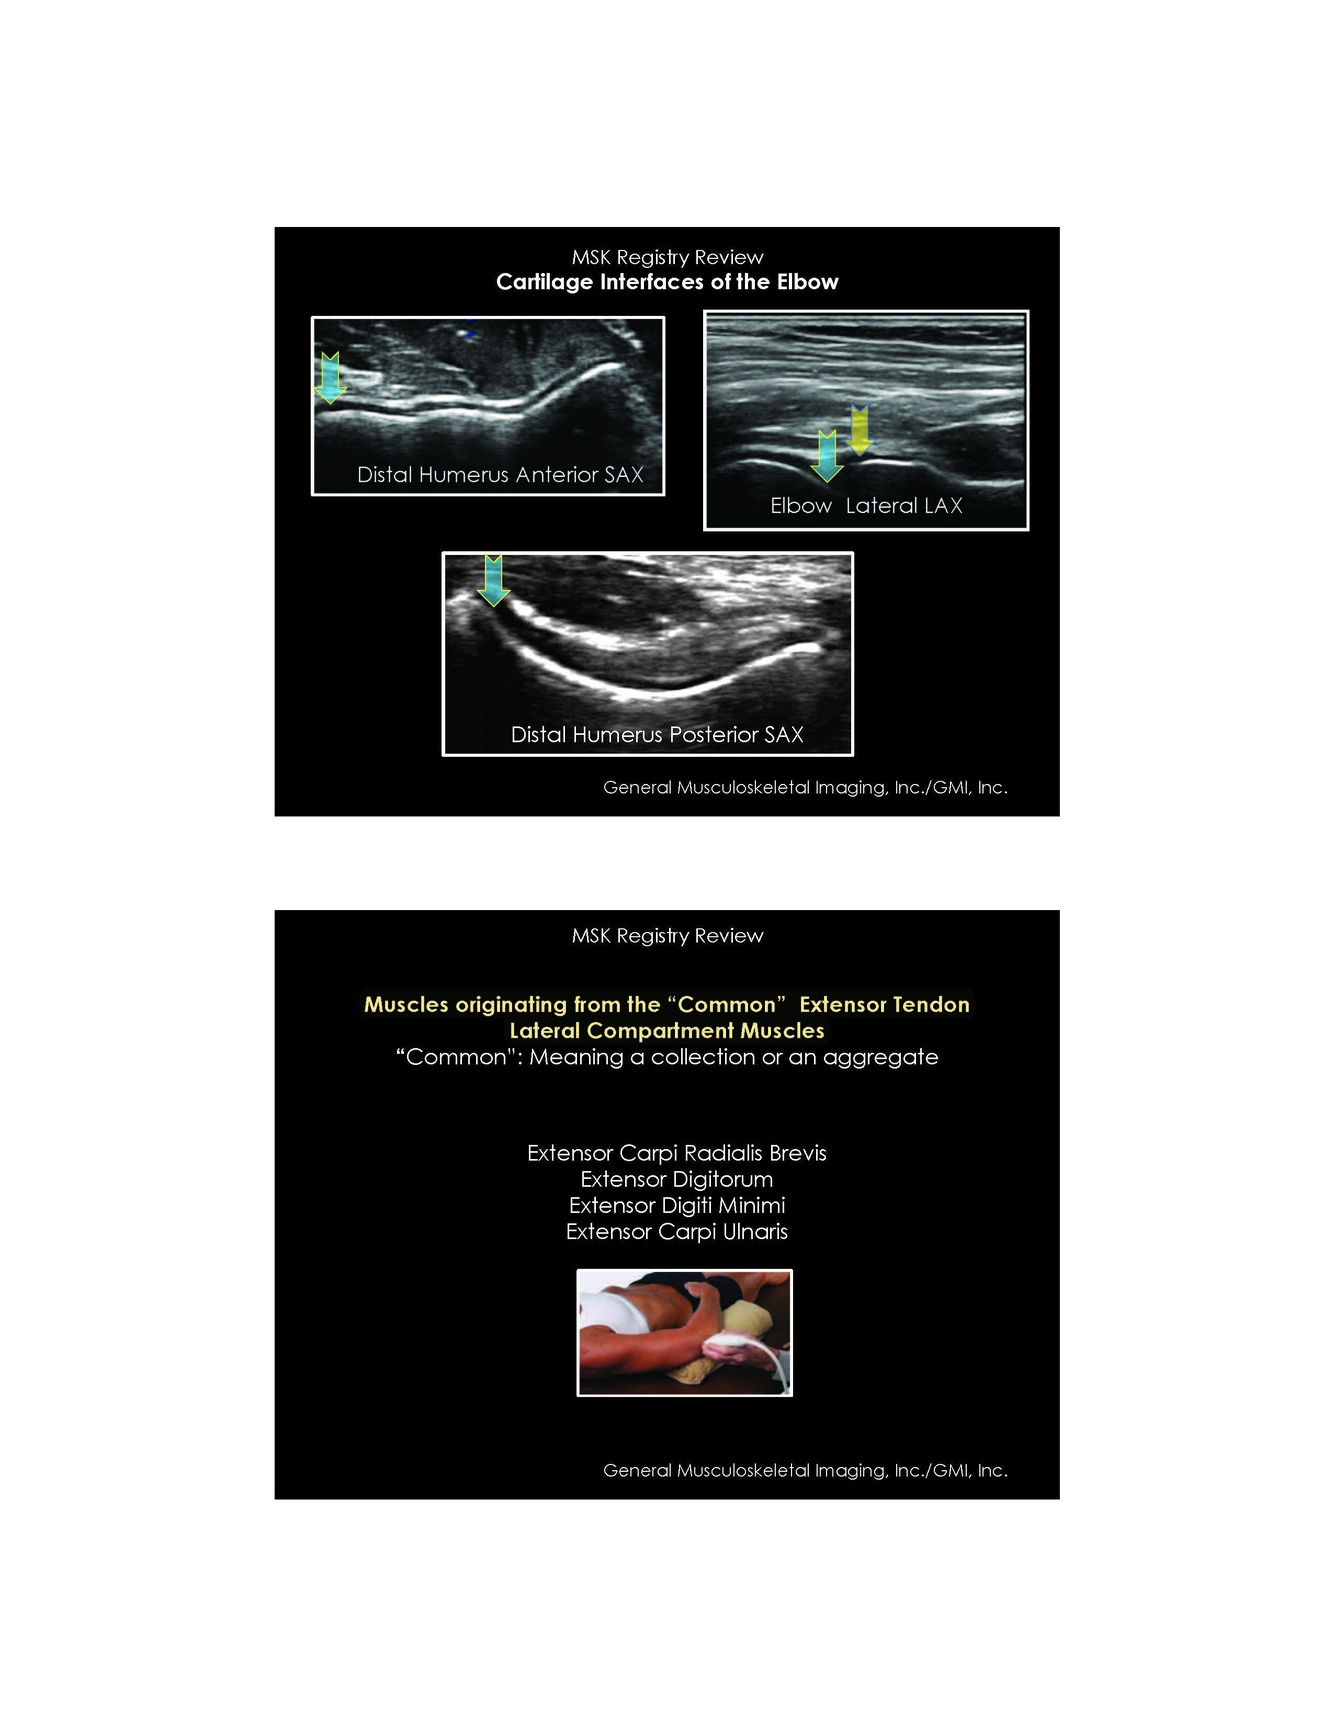

Name the 4 muscles orginating from the common extensor tendon Lateral compatment

ECRB ED EDM ECU